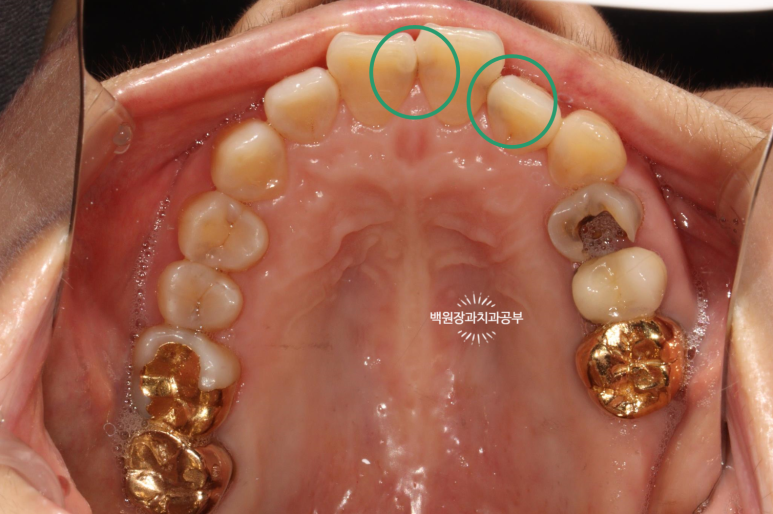

서론이 길었네요. 60대 여자 환자분이시고 위 앞니 사이사이에 있는 인접면 충치 치료차 내원하셨습니다.

정면을 보면, 치아 사이사이에 있는 충치가 얼핏 보이실거에요!

하얀것은 치아고 까만것은 충치라는걸 유치원생도 다 구분할 수 있을거에요. ㅎㅎㅎ

위턱 앞니의 사이사이마다 인접면 충치가 보이네요...

더 확실하게 보여드리기 위해 고개를 살짝 돌려서 보면..

고개를 돌려서 보면 인접면 충치를 더 잘 확인하실 수 있습니다!

집에서 확인해 보실 때도 고개를 돌려서 보셨었겠죠?

치과의사만 볼 수 있는 치아 뒷면 !!

사실 자기 앞니의 뒷면을 본 다는 것이 쉽지는 않습니다만..

치과의사는 뒷면을 볼 수 있습니다 !!!

딱 보아도 충치가 있는 걸 아실 수 있죠?

까맣게 보이는 부위들이 치아 옆면의 충치들입니다.